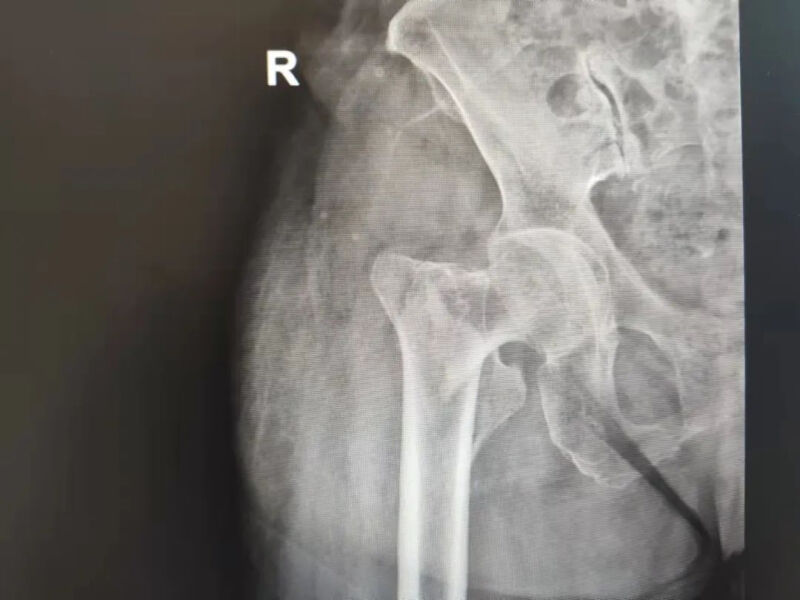

11月17日,一个平常的傍晚,87岁的杨奶奶(化名)吃完饭照常在养老院里散步,却不慎摔倒,右腿着地,当即右髋关节一阵疼痛就站不起来了。幸好养老院工作人员及时发现,立马联系了医务室。只见杨奶奶右下肢明显肿胀,越来越疼,为进一步诊治,便将她送到深圳禾正医院。禾正医院骨科主任医师林尊文接诊后,经过详细检查和右侧髋关节正侧位片提示,杨奶奶被确诊为右股骨粗隆间骨折。

右侧髋关节正侧位片